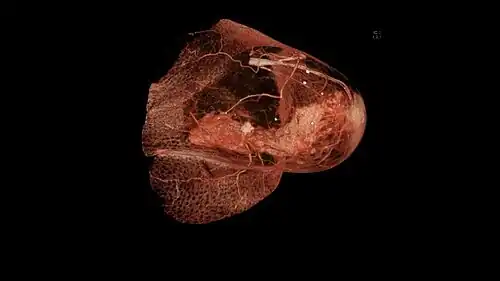

Nach der Operation wird das aus der Brustdrüse entfernte Operationspräparat in der histologischen Untersuchung auf seine exakte Größe gemessen und das Gewebe auf weiteren Befall untersucht. Die entfernten Lymphknoten werden auf Metastasen geprüft. Die Größe des Karzinoms und die Anzahl der befallenen Lymphknoten sind für die TNM-Klassifikation, Prognose und weitere Behandlung von Bedeutung. Das Operationspräparat wird auch daraufhin vermessen, ob der Abstand zwischen dem Karzinom und dem verbliebenen, gesunden Gewebe ausreichend groß ist. Sollte dies nicht der Fall sein, kann eine Nachoperation nötig werden, damit ein angemessener Sicherheitsabstand zwischen gesundem und erkranktem Gewebe erreicht wird.

Die Klassifikation eines Tumors ist dessen exakte Beschreibung auf der Grundlage der pathologischen Untersuchung einer Gewebeprobe oder des OP-Präparats und der entnommenen Lymphknoten.